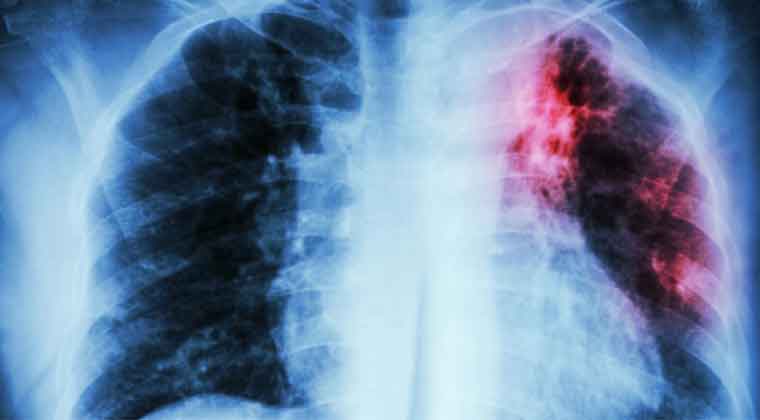

السُل مرض معدٍ خطير يُصيب الرئتين في الأساس. تنتقل البكتيريا التي تتسبَّب في الإصابة بمرض السُل من شخص إلى آخر من خلال الرذاذ الذي يخرج في الهواء عبر السعال والعطس. بعدما كان هذا المرض نادرًا في البلدان النامية، بدأت حالات عدوى السُّل في التزايد في عام 1985 ، ويرجع ذلك -إلى حد ما- إلى ظهور فيروس نقص المناعة البشرية، وهو الفيروس الذي يتسبَّب في الإصابة بالإيدز.

كما يمكن أن يصيب داء السل أجزاءً أخرى من الجسم، مثل الكلى أو العمود الفقري أو الدماغ. وعندما تحدث الإصابة داء السل خارج الرئتين، تختلف العلامات والأعراض وفقًا للعضو المصاب. فعلى سبيل المثال، قد يتسبب داء السل الذي يصيب العمود الفقري في الشعور بألم في الظهر، بينما قد يتسبب مرض السل الذي يصيب الكلى في وجود دم في البول.